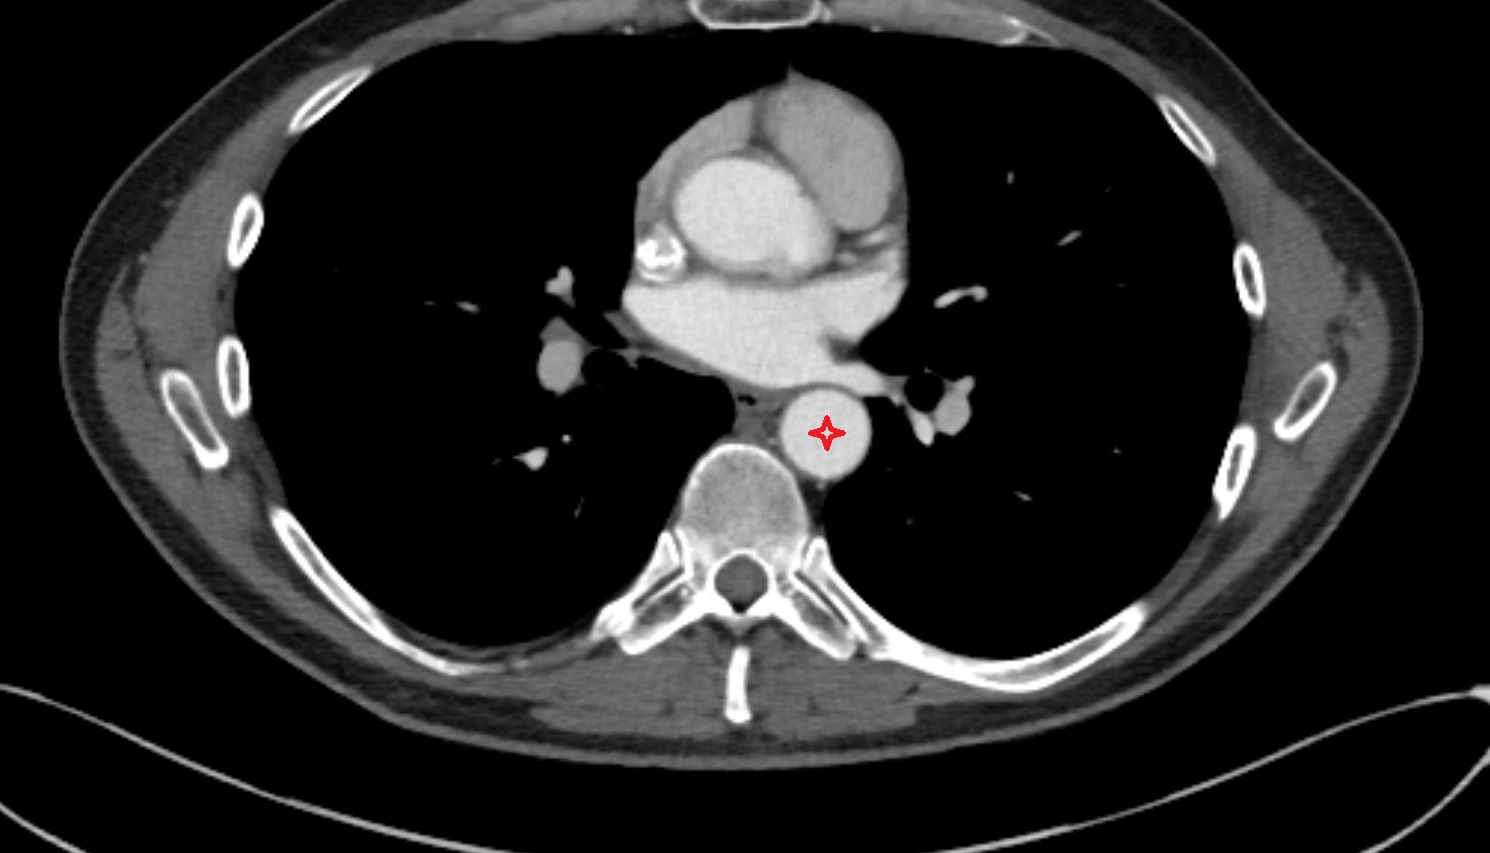

- Thoracic part of esophagus

- Descending thoracic aorta

- Esophagus